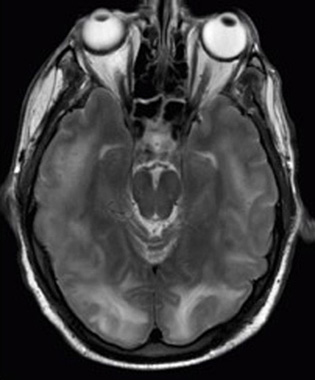

M R I scan of a brain with specific tumors.

Figure 4. These two applications of physics have more in common than meets the eye. Microwave ovens use electromagnetic waves to heat food. Magnetic resonance imaging (MRI) also uses electromagnetic waves to yield an image of the brain, from which the exact location of tumors can be determined. (credit: Rashmi Chawla, Daniel Smith, and Paul E. Marik).